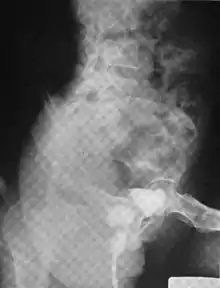

Another view of a urethral diverticulum seen on urethrogram

Urethral diverticulum is often an incidental finding.[2] It can be diagnosed using magnetic resonance imaging and/or micturating cystourethrography.[1] Other studies that can be used to diagnose urethral diverticulum include intravenous urography, urethroscopy, and/or ultrasound. Conditions that should be distinguished from urethral diverticulum in a differential diagnosis include overactive bladder, Gartner's duct cyst, Gartner's duct abscess, ectopic caeco-ureterocele, interstitial cystitis, pelvic inflammatory disease, endometriosis, and cancer.[3]